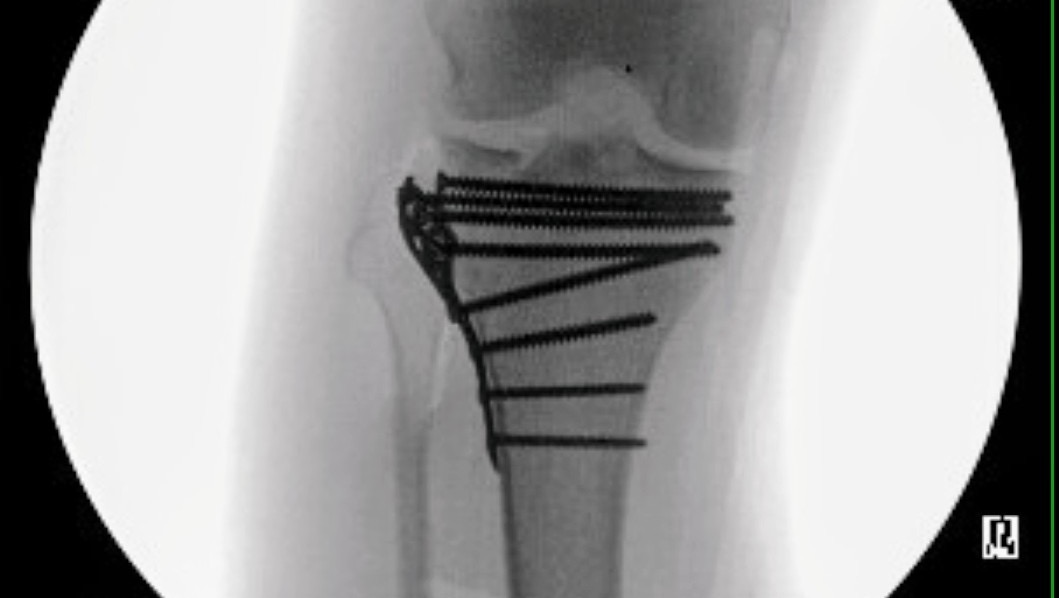

Last weekend, Josh and I went to Carolina Beach to celebrate my daughter's 13th birthday. After only a few minutes in shallow water, he was hit by a kid's surfboard and knocked down by the waves. Of all the bad luck, the surfboard managed to fracture his right tibial plateau, smashing the surface where his femur meets the lower leg. We were able to get him into surgery on July 18th at UNC, and after several hours, he came out with a lot more metal in his knee and a cool new brace.